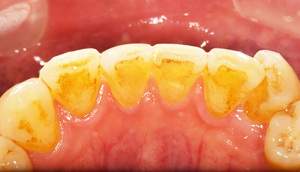

歯石除去

治療前

治療後

| 年齢 | 36歳・男性 |

| 主訴 | 歯石をとりたい |

| 治療内容 | 歯石除去 |

| 治療期間 | 30分 |

| 費用 | 約2,000円 |

| リスク・副作用 | ・歯ぐきの炎症が強いと歯石を取る際に出血することがあります。 ・処置後に歯がしみることがあります。 ・歯と歯の間に隙間ができるので、息が漏れ発音しにくいと感じることがあります。 ・歯ぐきの炎症が軽減すると歯ぐきが引き締まり、歯が長く見えることがあります。 |